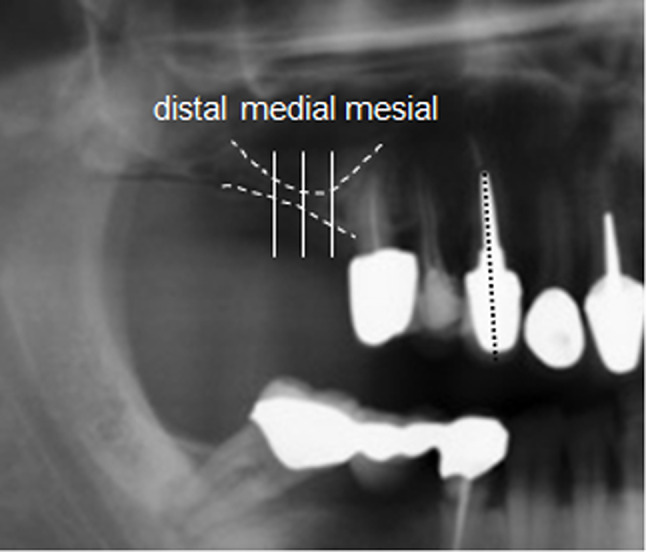

Materials and methods: A total of n = 29 patients (14 females, 15 males) with a mean age of 55.4 ± 10.0 years and reduced volume of the alveolar ridge were retrospectively analyzed after treatment with 34 HVSOs in the maxilla and mandible. After controlled clinical follow-up of six months after augmentation, enossal implantation of 79 implants (maxilla 45, mandible 34) was performed. A standardized two-dimensional radiological assessment with panoramic tomography (OPTG) of the augmented bone height and clinical evaluation of the implants was performed over a mean follow-up period of 2.3 years.

Results: HVSO resulted in a significant increase in vertical bone height by 4.4 mm ± 2.0 mm (mean vertical gain: +59.4%) with + 101% in the maxilla and + 27.5% in the mandible directly after the procedure (T1), with both p < 0.001. After a mean observation period of 2.3 years bone height remained stable with a total gain of 41.4% (maxilla: 72.6%, mandible: 18.6%), with p < 0.001 and p = 0.001, respectively. Overall implant survival rate was 91% (maxilla: 89%; mandible: 94%).